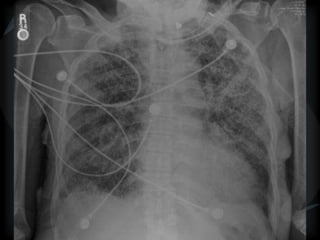

Mosaic CT Patterns Ground glass – inflammation/ fibrosis  airway obstruction (best seen on expiration) • COPD • small airway disease  Vascular obstruction • chronic thrombotic pulmonary hypertension • sickle cell disease • vasculitis

Mosaic CT Patterns

 Ground glass – inflammation/ fibrosis

 airway obstruction (best seen on expiration)

• COPD

• small airway disease

 Vascular obstruction

• chronic thrombotic pulmonary hypertension

• sickle cell disease

• vasculitis